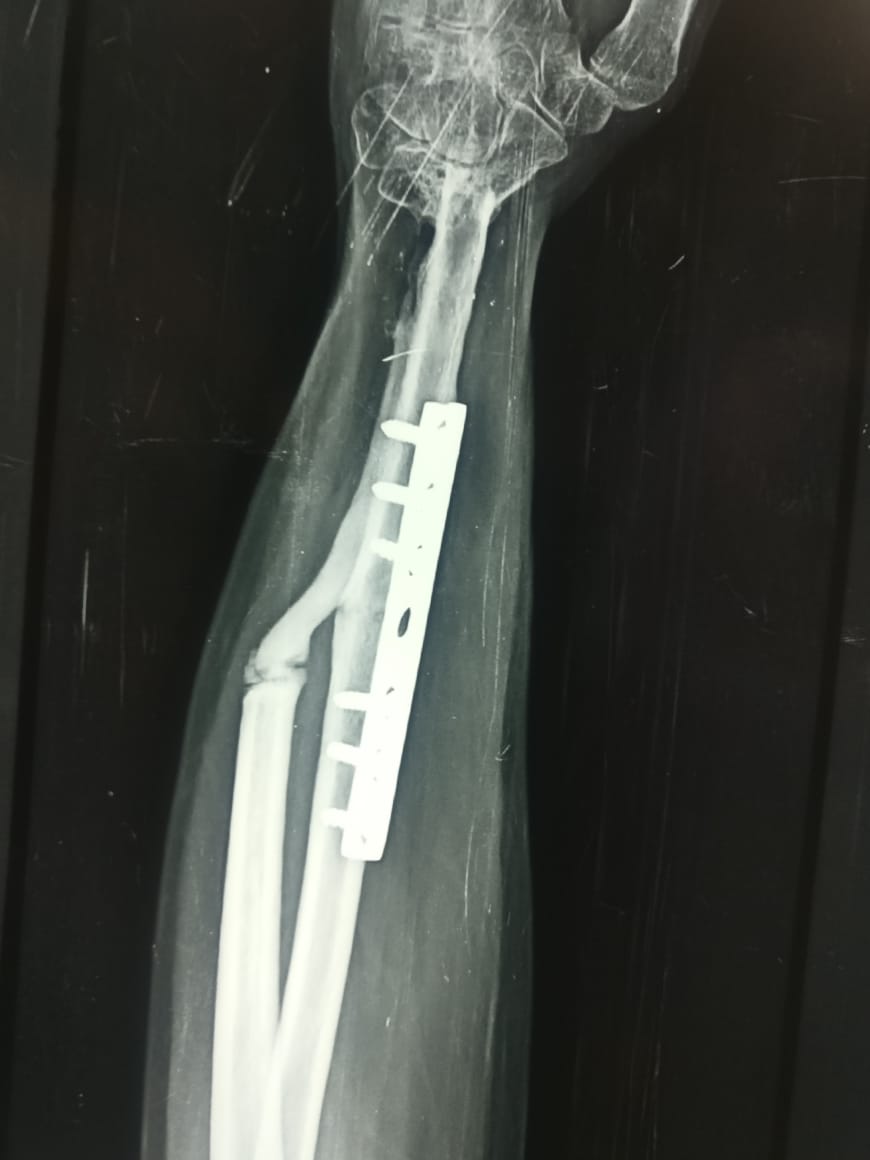

Translocation of Ulna for GCT Of Distal Radius